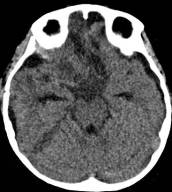

病例1:患儿男性,9岁。因反复出现意识丧失、视力下降半年收入院。入院后CT及 MRI显示颅内有形态不规则、“超大型”的颅咽管瘤,最大径约10厘米,见图1、图2。

图2.术前MRI

白色箭头指示肿瘤下极达枕大孔区